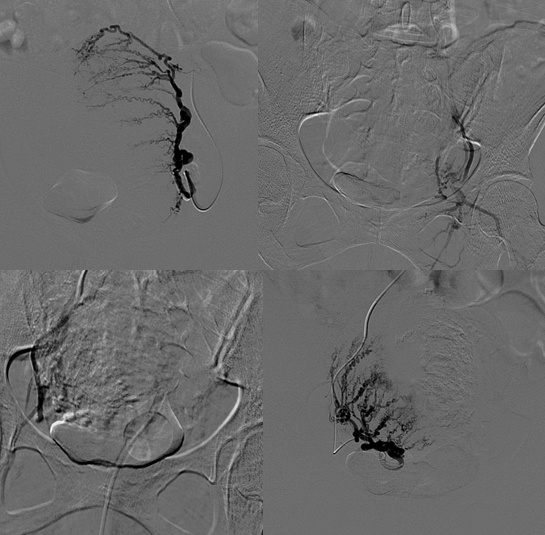

通过磁共振检查与妇检病理排除其他恶性疾病,曾女士适合通过左手“打针”行介入微创栓塞保留子宫的治疗方法治疗,则给予曾女士行子宫腺肌病超选择介入栓塞治疗。经左手打针超选择栓塞子宫腺肌症的营养血管,曾女士的子宫腺肌症血供丰富、生长旺盛,双侧子宫动脉供血(如下图)。